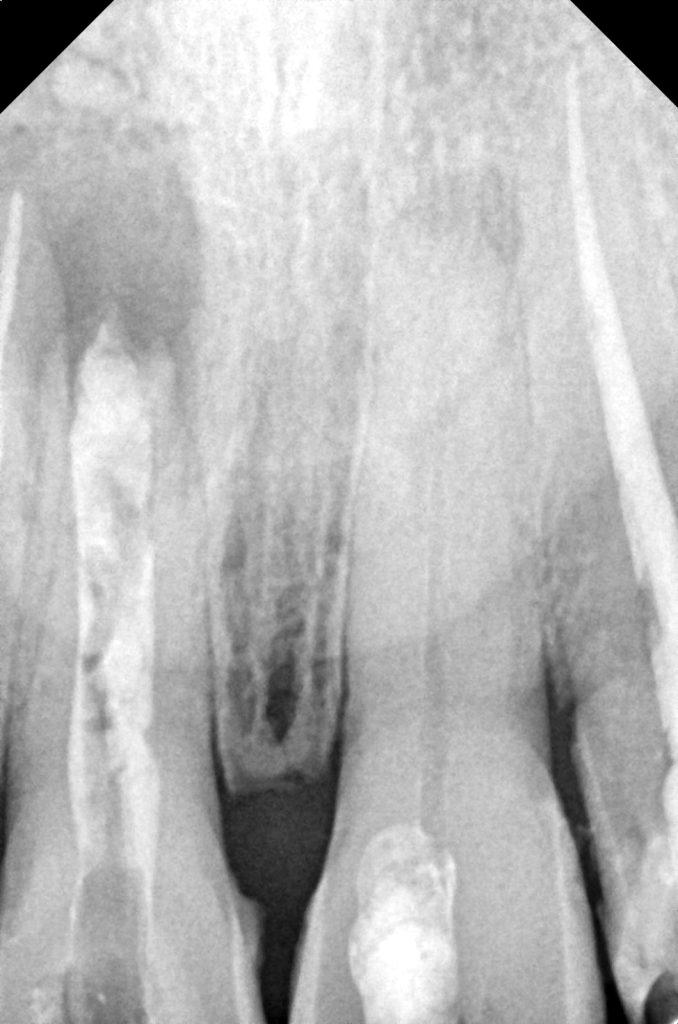

- Prior root canal therapy with open apex—managed using MTA-based apexification.

- Post-traumatic discoloration due to pulpal necrosis.

- Residual esthetic defect after apexification.

Previous MTA apexification provided apical stability, allowing safe buildup and crown retention. Non-vital bleaching minimized aggressive preparation and preserved tooth structure.